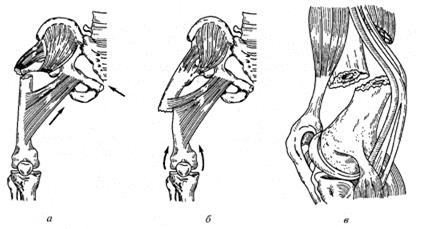

Классификация переломов диафиза бедренной кости: Иллюстрации и информация